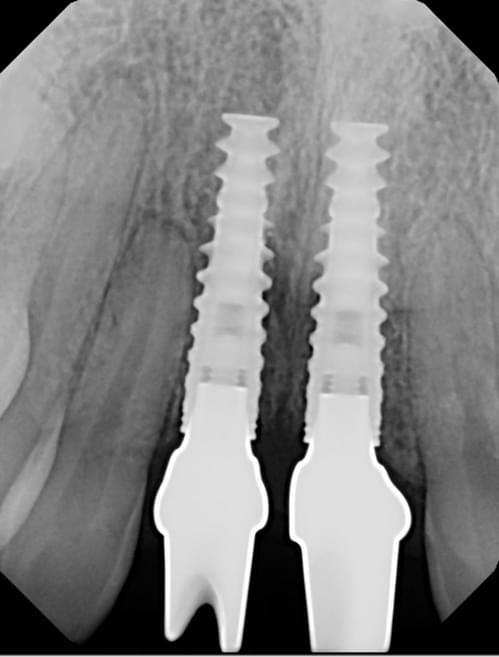

Single Implant Replacing two missing front teeth:

Single Implants replacing two Front teeth